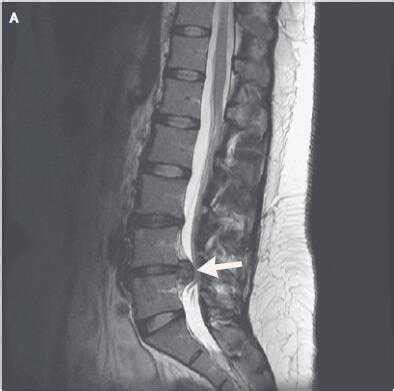

磁共振检查:跟CT一样,具有确诊价值,同时由于其成像原理,对于观察神经以及是否存在神经压迫水肿信号,有独特的优势,也是目前诊断腰椎间盘突出,明确神经压迫的主要检查,老百姓没学过医的也可以看得到的“突出”!

症状是典型的腰腿痛症状,还伴有麻木(灯泡一闪一闪了)神经异常放电,当时还没有学医的我去了家里的镇医院做了一个磁共振检查,当时拿到黑胶片的时候,连一个刚成年的我都看到了我那明显突出的“椎间盘”,白白的亮闪闪的......